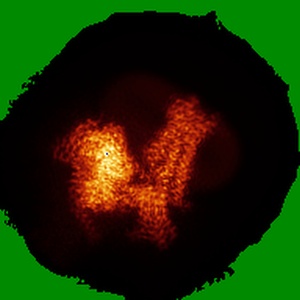

Cryo-EM structure of the immepip-bound H3R-Gi complex

Single-particle3.0 Å